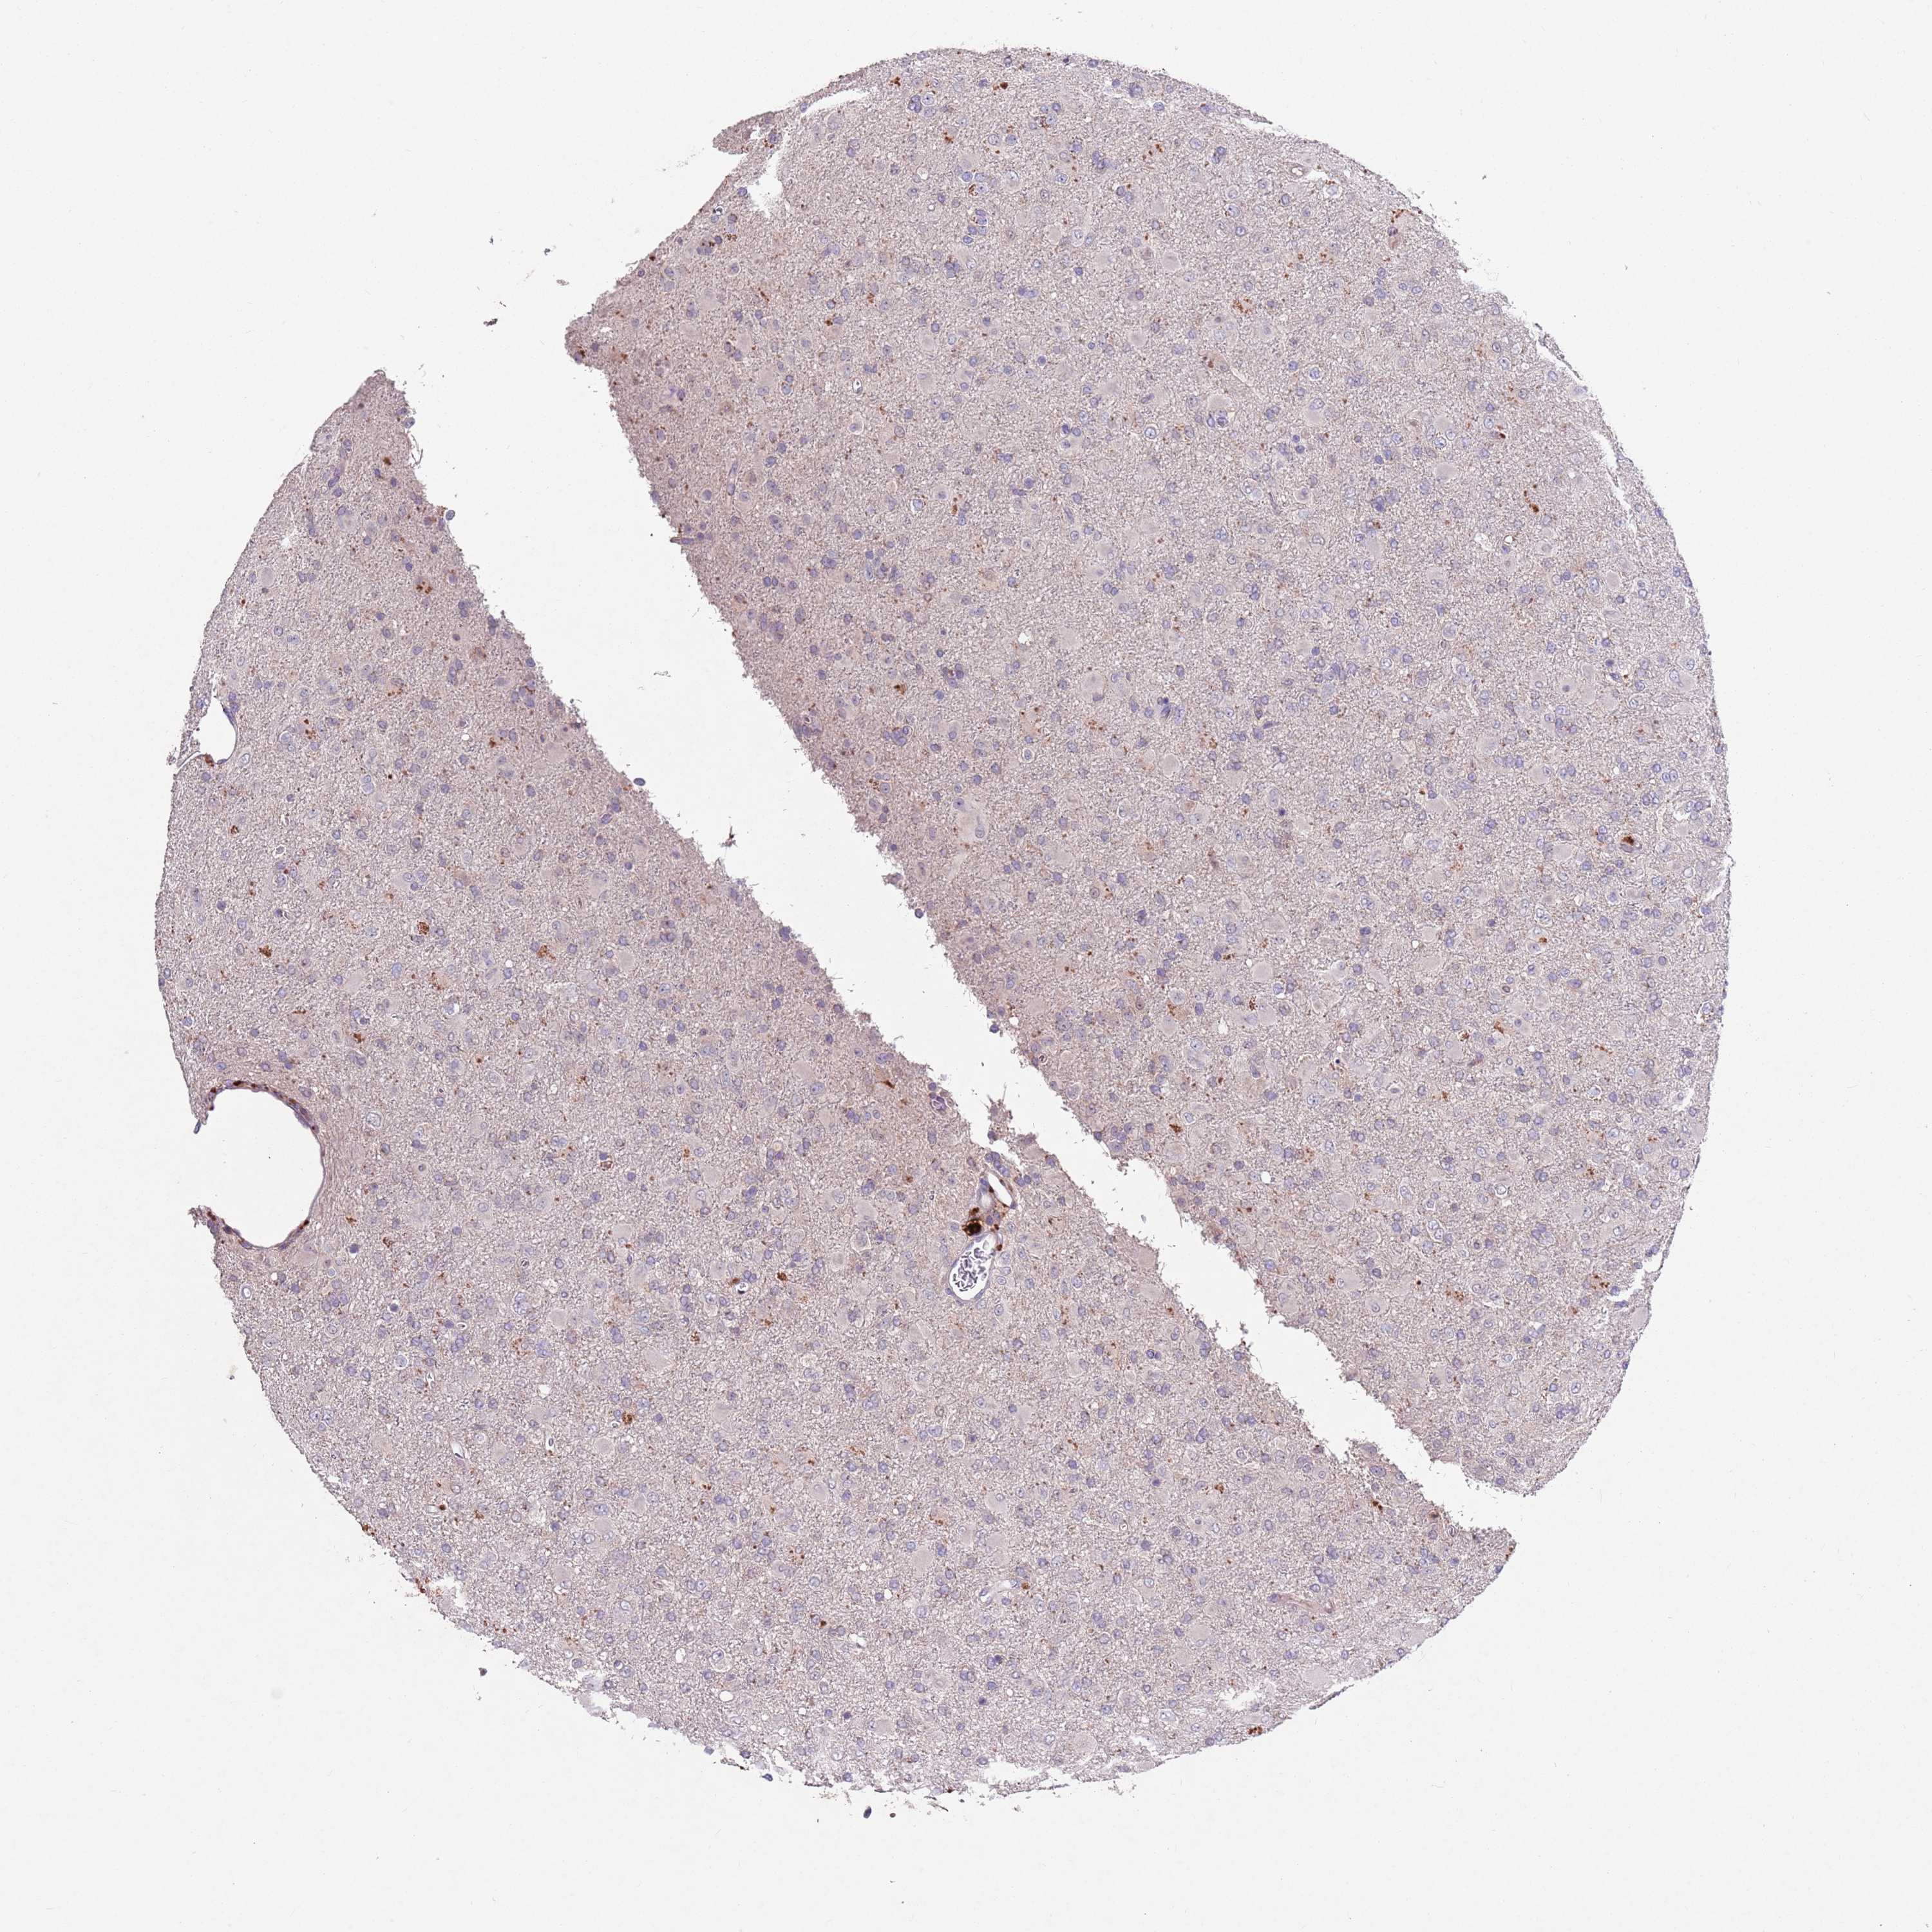

GLIOMA - Protein expressioni

A mouse-over function shows sample information and annotation data. Click on an image to view it in a full screen mode. Samples can be filtered based on level of antibody staining by selecting one or several of the following categories: high, medium, low and not detected. The assay and annotation is described here.

Note that samples used for immunohistochemistry by the Human Protein Atlas do not correspond to samples in the TCGA dataset.

Antibody stainingi

Antibody staining in the annotated cell types in the current human tissue is reported as not detected, low, medium, or high, based on conventional immunohistochemistry profiling in selected tissues. This score is based on the combination of the staining intensity and fraction of stained cells.

Each image is clickable and will lead to virtual microscopy that enables deeper exploration of all samples and also displays staining intensity scores, fraction scores and subcellular localization as well as patient and tissue information for each sample.

Antibody HPA047050

Antibody HPA050583

Glioma, malignant, High grade

Glioma, malignant, Low grade

Glioblastoma, NOS